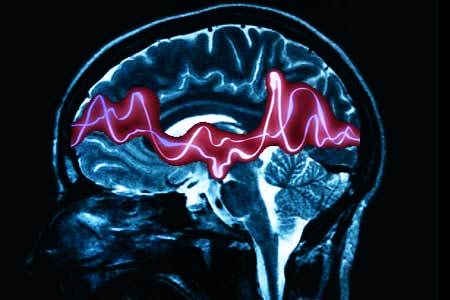

Эпилепсия — это хроническое неврологическое заболевание, которое может значительно влиять на качество жизни пациента. Многие люди задаются вопросом о возможности хирургического вмешательства. Операция может быть показана в случаях, когда медикаментозное лечение не приносит желаемых результатов, и приступы продолжаются, угрожая здоровью и безопасности пациента. Основными показаниями для операции являются частые и тяжелые приступы, которые локализованы в определенной области мозга. Однако существуют и противопоказания: это могут быть сопутствующие заболевания, наличие других неврологических расстройств или же неясная причина эпилепсии. Важно, чтобы решение о хирургическом вмешательстве принималось совместно с опытной командой специалистов, включая неврологов и нейрохирургов, после тщательной диагностики и оценки всех рисков.

Врачи отмечают, что хирургическое вмешательство при эпилепсии может быть эффективным методом лечения, особенно в случаях, когда медикаментозная терапия не приносит желаемых результатов. Показания к операции включают частые и тяжелые приступы, которые значительно ухудшают качество жизни пациента, а также наличие определенных структурных изменений в мозге, таких как опухоли или аномалии развития. Однако не все пациенты подходят для хирургического лечения. Противопоказания могут включать наличие серьезных сопутствующих заболеваний, психические расстройства или отсутствие четкой локализации очага эпилепсии. Врачи подчеркивают важность индивидуального подхода и тщательной оценки состояния пациента перед принятием решения о хирургическом вмешательстве.

- Электроэнцефалография (ЭЭГ) — регистрирует мозговые волны посредством электродов, размещенных на волосистой части головы. ЭЭГ помогает диагностировать нарушения головного мозга, обнаруживая аномальную электрическую активность в головном мозге.

- Магнитно-резонансная томография (МРТ). МРТ использует магнитные поля и компьютер для создания изображений структуры мозга. Томография создает четкое изображение, которое может выявить аномалии мозга.